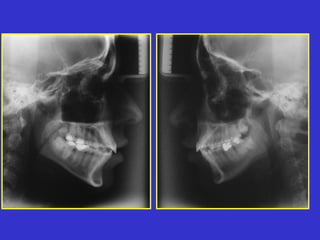

Este documento describe las diferentes proyecciones radiográficas utilizadas para examinar los senos paranasales, incluyendo las proyecciones básicas de Caldwell, Waters lateral y las proyecciones especiales como Hirtz y Waters mentonasal. También describe las diferentes estructuras anatómicas que componen el complejo ostiomeatal anterior y posterior de los senos paranasales.